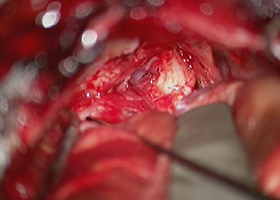

[画像所見]

-

体位 -

開頭 -

左後下小脳動脈(黄色矢印)が

左舌咽神経を圧迫 -

左後下小脳動脈を手前に移動 -

減圧完了